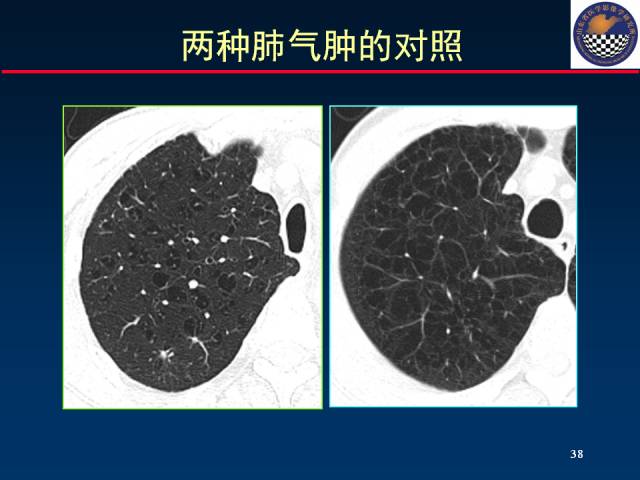

①小叶中心型肺气肿;

②全小叶型肺气肿;

小叶中心型、全小叶型及间隔旁肺气肿常见于慢性支气管炎、各种原因的肺间质纤维化及支气管哮喘等。小叶中心型(需CT诊断)及全小叶型肺气肿可融合成大泡。

(1)肺纹理减少型:这种肺气肿的三项主要X线表现为:①肺过度充气膨胀;②肺血管纹理减少;③肺大泡。肺过度充气膨胀,表现为肺透亮度加深和肺容积增大。肺容积增大表现横膈位置下降和膈顶变平、胸骨后肺透亮区增宽、胸廓呈桶状及心影呈垂直型。这种类型常多见于全小叶型肺气肿。

(2)肺纹理增多型:其X线表现肺纹理不是纤细减少,反而比正常者更为显著。有的轮廓不规则、不清晰,提示有严重的慢性支气管炎现象。肺部只有轻度或中度的过度肺充气膨胀(肺大泡很少见到)。这种类型多见于小叶中央型肺气肿。